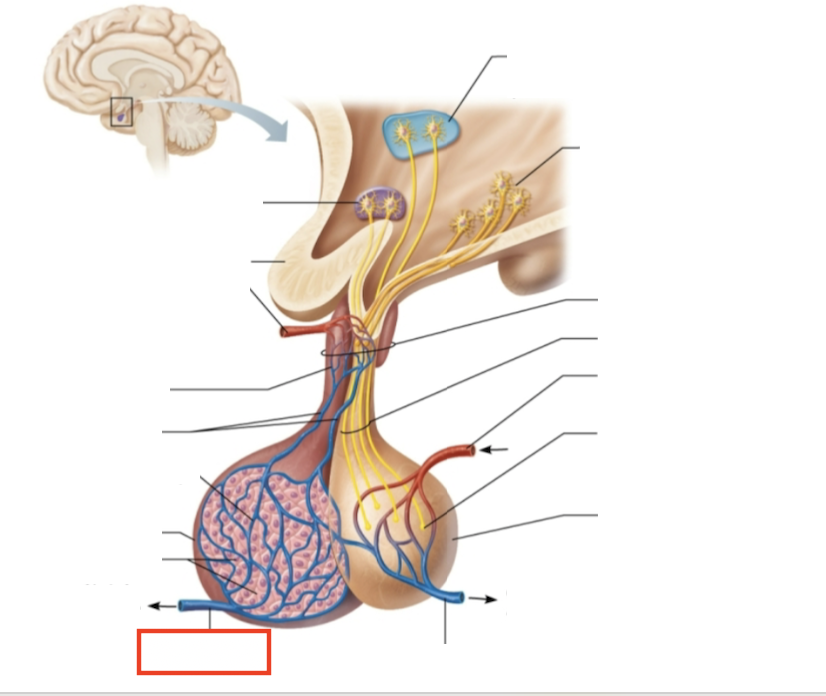

What structure is highlighted?

testes (male)

What are the target organs and effects of testosterone?

most cells of the body; promotes the maturation of the male reproductive organs, the development of secondary sex characteristics, sperm production, and sex drive

What hormone is produced by the testes?

testosterone

What stimulates testosterone production?

LH and FSH